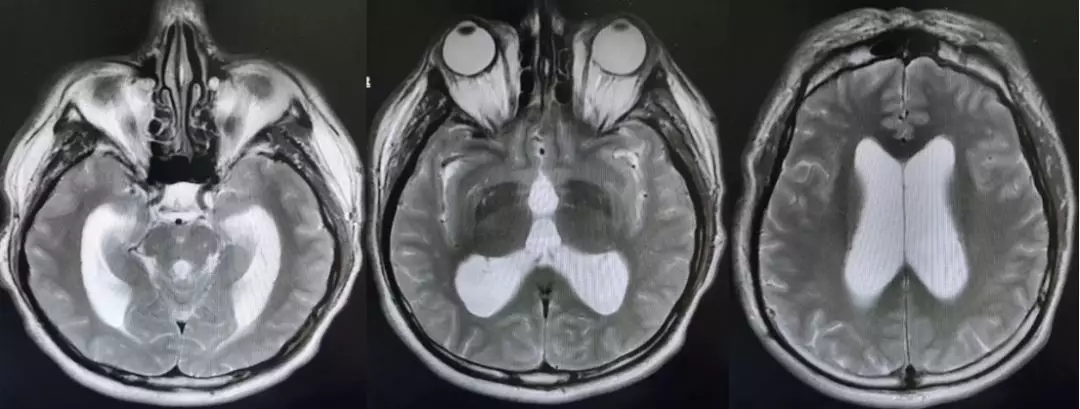

颅脑核磁T2W1成像

第四脑室内见一巨大形态不规则的异常信号影,肿瘤信号不均匀,T1W1呈略低信号影,T2W1呈稍高及高信号影,增强扫描可见肿瘤不均匀明显强化。肿瘤充满整个四脑室,大小约44*37*55mm,上方接近四脑室顶部,下方至颈2脊髓平面上方,已经部分侵袭桥脑、延髓,局部边界不清,无明显间隙,脑干局部明显受压变形。肿瘤上方脑室系统扩张,出现梗阻性脑积水征象。

影像诊断:1.第四脑室内占位性病变,室管膜瘤可能性大;2.梗阻性脑积水。